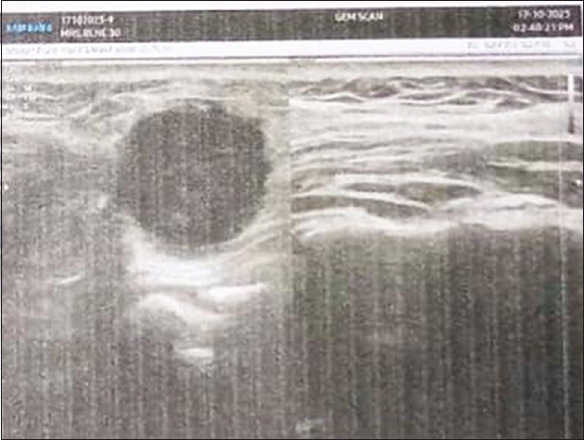

良性平滑肌肿瘤,称为平滑肌瘤,比较常见,子宫病例占95%的发病率。口腔平滑肌瘤通常表现为舌头、硬腭或颊粘膜下缓慢生长的无症状肿块。平滑肌瘤有三种组织学类型:上皮样平滑肌瘤、实体平滑肌瘤和血管平滑肌瘤。影响口腔的最常见的平滑肌瘤类型是称为血管平滑肌瘤的孤立形式,通常发生在皮下。诊断通常由组织病理学和免疫组织化学(IHC)程序确定。本病例报告一30岁女性患者,右脸颊区域有病变。术后标本常规处理,苏木精和伊红染色,免疫组化研究证实诊断为“良性梭形细胞瘤-血管平滑肌瘤”。

Benign smooth muscle tumours, known as leiomyomas, are comparatively frequent, with uterine cases accounting for 95% incidence. Oral leiomyomas typically appear as asymptomatic, slowly-growing submucosal lumps in the tongue, hard palate, or buccal mucosa. Three histologic kinds of leiomyomas are recognized: epithelioid leiomyoma, solid leiomyoma, and angioleiomyoma. The most prevalent type of leiomyomas affecting the oral cavity are solitary forms called angioleiomyomas, which typically develop in the subcutis. The diagnosis is commonly determined by histopathological and Immunohistochemistry (IHC) procedures. This case reports a 30-year-old female patient with a lesion on her right cheek region. The postsurgical specimen was routinely processed and stained with hematoxylin and eosin staining, and IHC studies confirmed the diagnosis of 'Benign spindle cell neoplasm-Angioleiomyoma'.